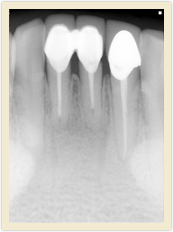

![]() |

| Before Photo | After Photo |